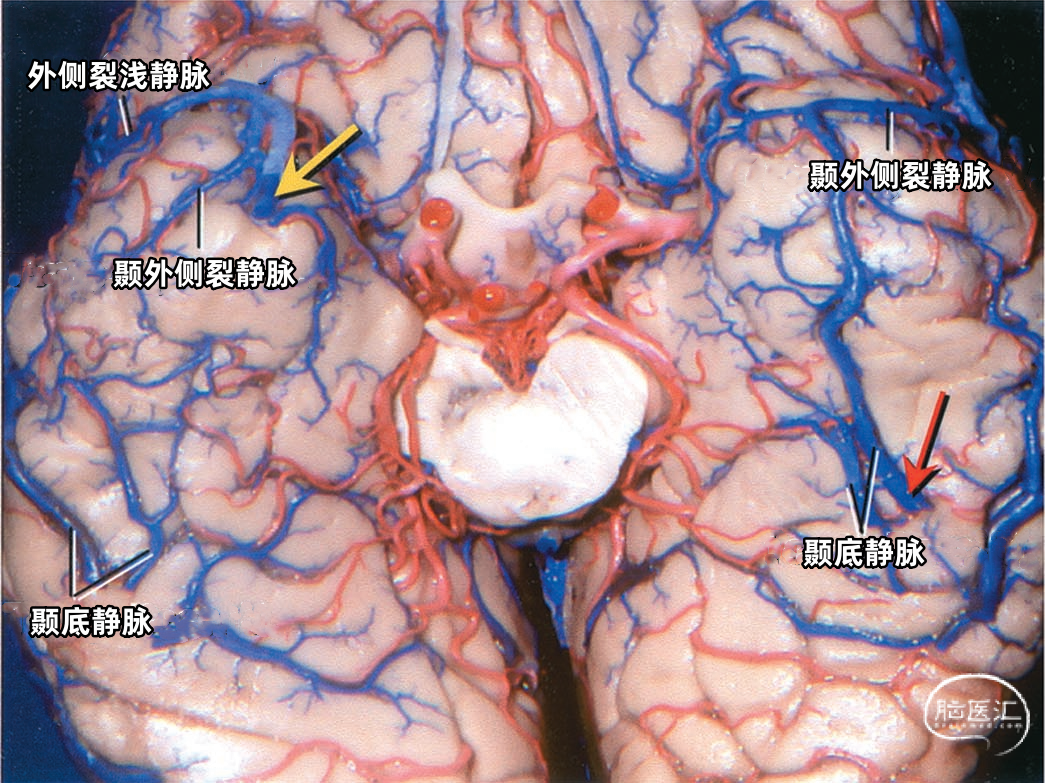

颞叶外侧面的皮层静脉可引流入横窦(上图),但在流入横窦之前,它们常向内沿颞叶底面进入小脑幕的短窦,此窦进入横窦末端之前在小脑幕内走行大约1cm。来自颞叶和枕叶底面的皮层静脉通常汇入外侧小脑幕窦。 Labbé静脉通常终于横窦(上图),但也可弧形围绕大脑半球下缘汇入外侧小脑幕窦。▼9.小脑幕窦

下图示汇入外侧小脑幕窦的颞底静脉、枕底静脉。左侧红色箭头指示左侧汇入小脑幕窦属支的颞底长静脉。颞底静脉汇入有多个属支的小脑幕窦。右侧黄色箭头显示汇入右侧小脑幕窦的静脉属支。 下图示(左侧)颞底静脉和枕底静脉汇聚于两个横窦内侧的短小脑幕窦。(右侧)Labbé静脉和颞后静脉直接引流入横窦。左侧小脑幕的另一个窦(小脑幕内侧窦)(黄色箭头)接受来自小脑的引流,向内侧经过小脑幕汇入窦汇。

下图示右侧枕底静脉,颞底静脉。从后颞下入路抬起颞底到达小脑幕游离缘时,除了可能牺牲Labbé静脉和来自颞叶、枕叶外侧面的静脉外,还可能需要牺牲多条汇入小脑幕窦的颞底静脉和枕底静脉。

下图示横窦和小脑幕窦的分支。抬起颞叶的后部,暴露进入横窦的Labbé静脉、颞后静脉和枕后静脉,从颞叶底面进入小脑幕窦的颞底静脉。

下图示颞叶底面。颞叶底面的前部由颞外侧裂静脉引流,并汇入外侧裂的静脉。右侧颞底静脉汇入靠近横窦内侧的小脑幕窦。 正常情况下由左侧前、中颞底静脉引流的区域,主要由一条沿着颞叶底面长轴向后走行的长干引流,且汇入小脑幕窦。黄色和红色箭头为汇入右侧和左侧小脑幕窦的静脉末端。

下图示汇入小脑幕窦的颞底静脉。红色箭头指示左侧汇入小脑幕窦属支的颞底长静脉。右侧颞底静脉汇入有多个属支的右侧小脑幕窦。